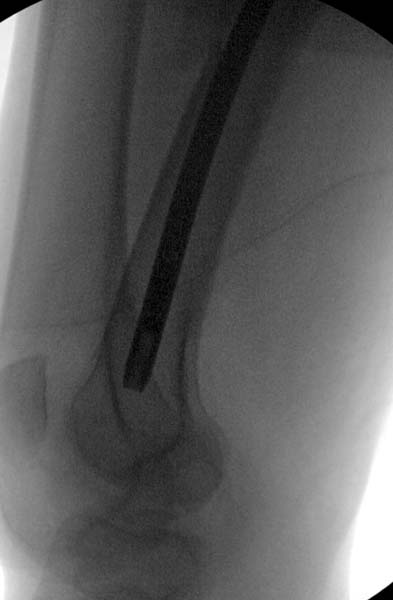

Около 11.00 вечера больная переведена в реанимацию, без сознания, но стабильная.. На третьий день провели стабилизацию перелома бедра антеградным остеосинтезом.

Закрытый БИОС решает множественные проблемы связанные с лечением переломов, но проблема дистальной блокировки без рентгена до сих пор остается нерешенной. Рекламированные производителями приспособления для дистальной блокировки из-за различной кривизны кости не эффективны или стоит очень дорого (Smith&Nephew SureLock). Задержка операции из-за блокировки не всегда удовлетворяет, и многих вынуждает искать альтернативные методы фиксации. С результатами таких действий, остеомиелитом и несращениями, встречаемся в ежедневной жизни..

Для решения проблемы дистальной блокировки компания DigiMed недавно предложила систему блокировки без рентгена. Пока в стране только два набора и только для антеградных гвоздей, но компания работает над созданием устроиства для других гвоздей тоже..

Результат первых случаев показала отсутствие разницы между занятиями на муляжах, а также Workshop и с удивительной точностью вывел латерально над кожей специальное сверло. Дальше по сверлу тонкий направитель и проводится сверление каннюлированным сверлом....